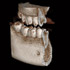

Höchste Bildqualität

X-ERA SMART verfügt über ein einzigartiges Patientenpositionierungssystem im 3D Bereich, das jede Bildverzerrung durch Patientenbewegung komplett ausschließt. Das Technologiekonzept erzeugt eine Bildqualität in extrem hoher Auflösung. Zwei verschiedene Aufnahmegrößen mit einer Voxel Größe von 80μm / 100 μm liefern in jeder Sichtfeldgröße (FoV) exzellente Ergebnisse für die weitere Diagnostik und Behandlung.

Nacholgend ein paar phänomenale Bilder & Werte,

die nicht nur einem Fachmann die Sprache verschlagen: